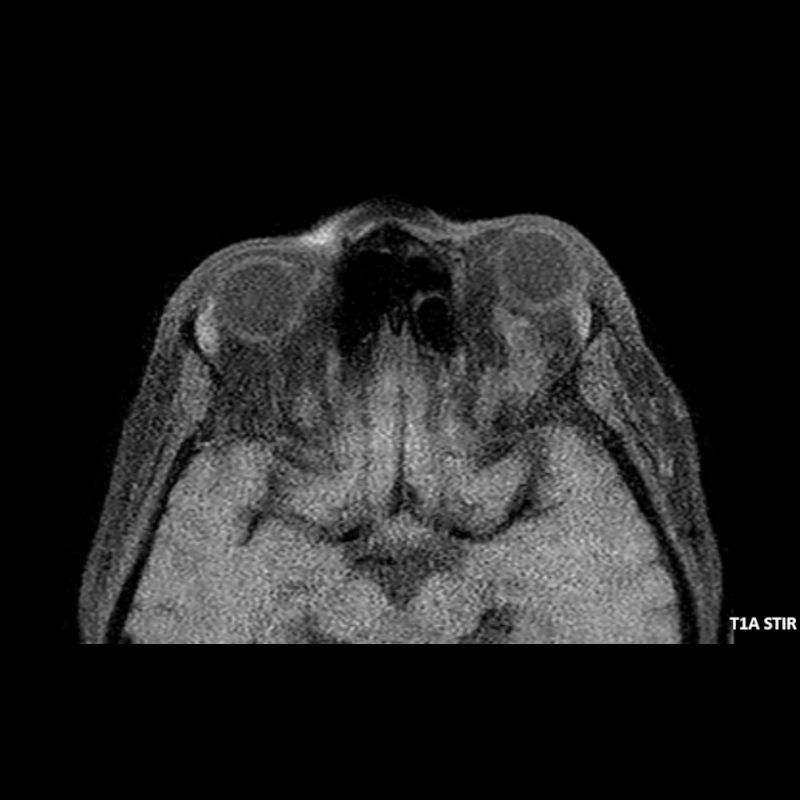

- A) Orbital MRG’de yağ baskılı T2A görüntülerde sol orbital globta ekzoftalmus (ok) izlenmiş olup retrobulbar yağlı dokuda kirlenmeler (ok) ve dilate superior oftalmik ven (ok) dikkati çekiyor. Beyin MRG’de kontrastlı T1A görüntüde sol kavernöz sinüste simetriğine oranla genişleme (ok) izleniyor.

- B) Pre ve post-kontrast yağ basklılı T1A görüntüler incelendiğinde superior oftalmik venin (oklar) kontrast madde verildikten sonra homojen dolum gösterdiği, dilate ve tortiyoze görünümde olduğu izleniyor.